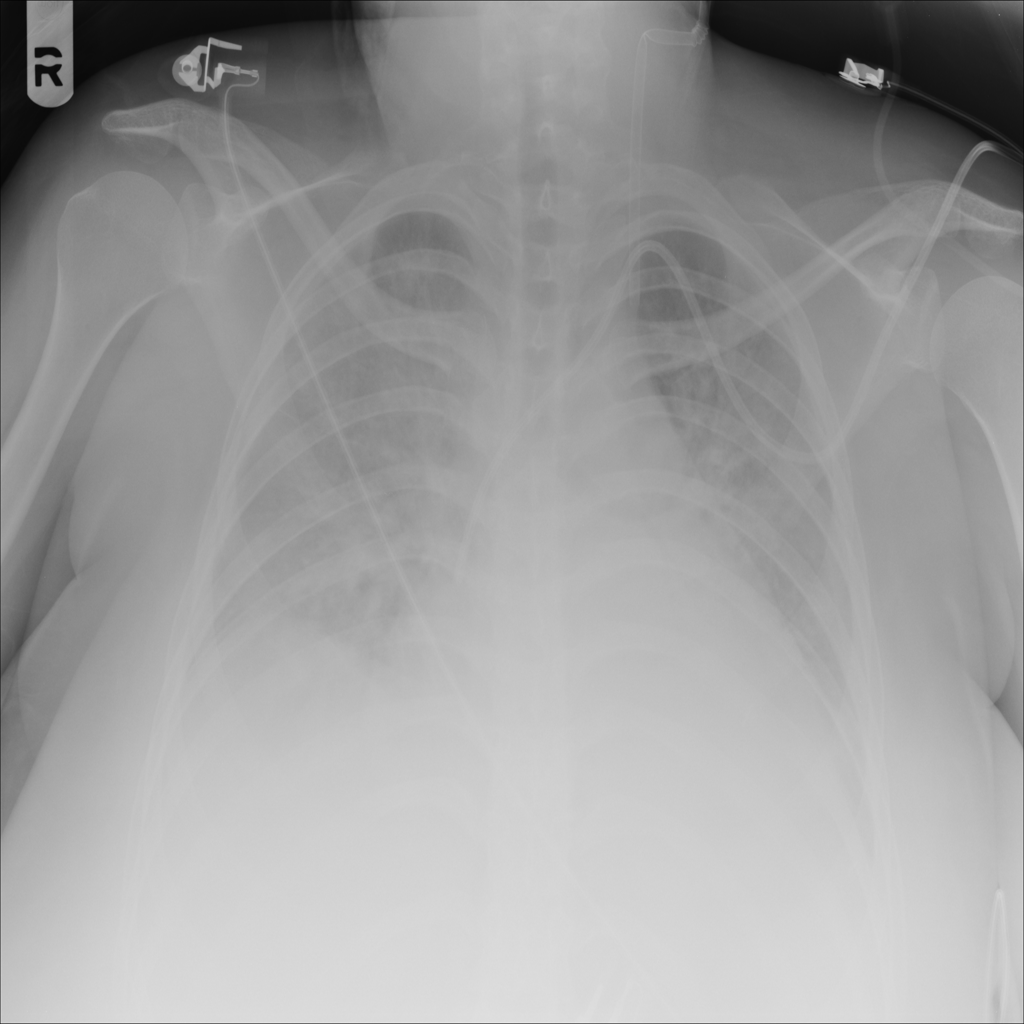

PAT-E828 · IMG-005Edema

PAT-E828 · IMG-005

AP